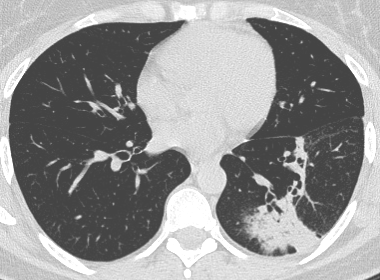

COVID19-CT dataset [51]: The dataset consists of a total of 746 CT images. There are 349 CT images of patients with COVID-19 and 397 CT images showing Non-COVID-19, but other pulmonary diseases. The positive CT images were collected from preprints about COVID-19 on medRxiv and bioRxiv, and they feature various manifestations of COVID-19. Since the CT images were taken from different sources, they have varying sizes between and . Figure 8 shows example CT images from the COVID19-CT dataset.

On the COVID19-CT dataset, the overall performance with respect to all evaluation metrics is inferior to that on the SARS-CoV-2 dataset. This can be attributed to the cross-source heterogeneity of the CT images in the dataset. The Non-COVID-19 CT images were taken from different sources and show diverse findings which pose difficulty to distinguish between COVID-19 and other findings associated with lung diseases due to the potential overlap of visual manifestations (see Figure 8). Another reason is that, the CT images in the COVID19-CT dataset show strong variations in contrast, variable spatial resolution and other visual characteristics, which could affect the model’s ability to extract more discriminative and generalizable features.